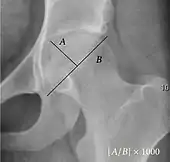

- Reimer's migration index (MI), also called the femoral extrusion index,[3] is calculated if hip dysplasia is detected. It can be used to indicate hip dislocation. It is the horizontal distance (parallel to the Hilgenreiner Line) between the Perkin line and the lateral border of the ossification center of the femoral head, divided by the horizontal width of the ossification center. The migration index is normally less than 33% by most sources,[9] but 25% and 30% has also been suggested.[10]

| Reimer's migration index[9] | ![]() |

The percentage of the femoral head that lies outside of the acetabular roof. It is also called the femoral extrusion index. | <25% |